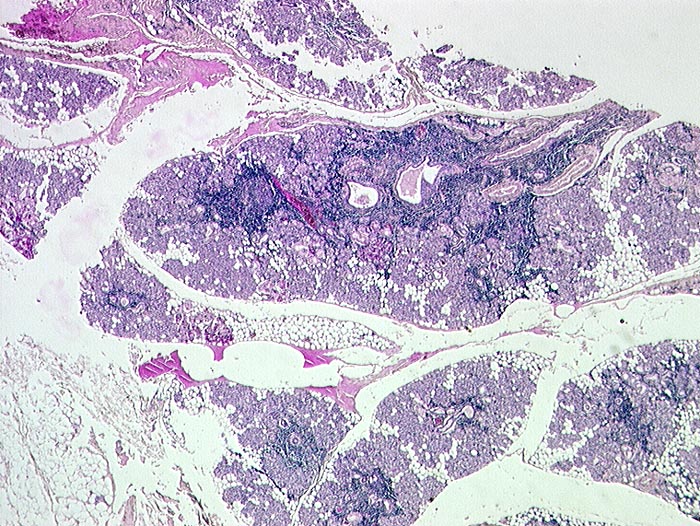

p/ Autoimmun- Sialadenitis bei Sjögren Syndrom

Autoimmun- Sialadenitis bei Sjögren Syndrom

Parotis

Das Zellbild ist je nach Stadium mehr oder weniger zellreich und zusammengesetzt aus Lymphozyten, Myoepithelien und selten Azinuszellen. Ein lymphozytäres Zellbild ist in Kombination mit dem typischen klinischen Bild (Keratokonjunktivitis sicca, Xerostomie, rheumatische Erkrankung) für die Sicherung der Diagnose ausreichend. Auf die Lippenbiopsie kann in diesem Fall verzichtet werden.